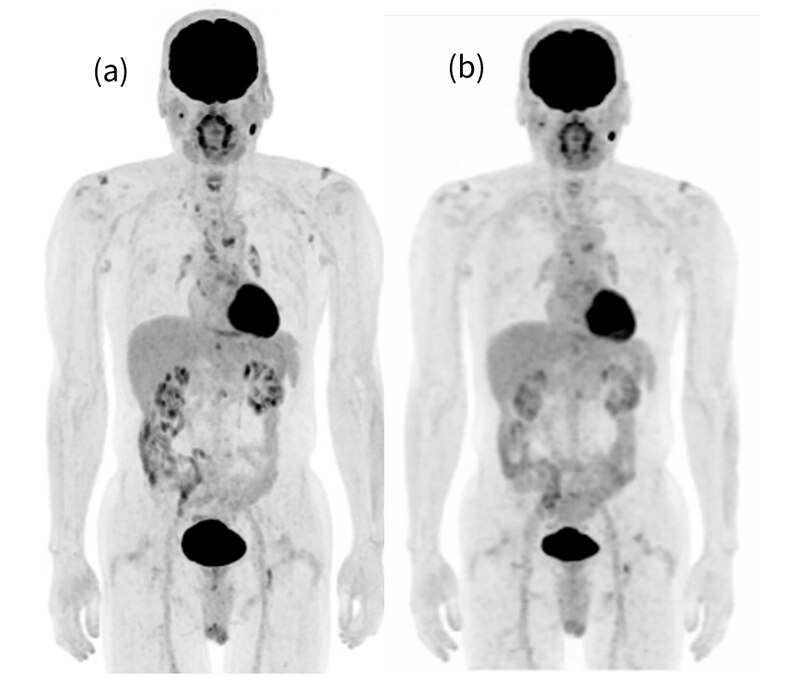

Advanced Motion Free(AMF)でのデバイスレス呼吸同期が可能であり、PETは特別な操作なくルーチンで呼吸同期が可能です。また、今回、PETとCTの呼吸同期(Motion Match)も実施できるようバリアン社の呼吸同期システムも導入し、CTとPETのミスレジストレーションの問題が解消できます。Direct MPR機能もあり撮影が終わったBedから確認ができるのでCTとPETのズレを検査中に把握することができます。BGOの装置であるため、TOFは搭載されていませんが、Deep Learningを用いた画像再構成であるPrecision DL(PDL)を搭載しており、TOF様の画像再構成が可能となっています。PDLはHigh、Medium、Lowと強度の異なる3パターンがあり好みの画質を選択することが出来ます。(図4,5)

図5. Q.ClearとPrecisionDLのPET Axial画像比較(β500) 膵頭部癌術後肝転移症例

(a) Q.Clear (b)LPDL (c)MPDL (d)HPDL